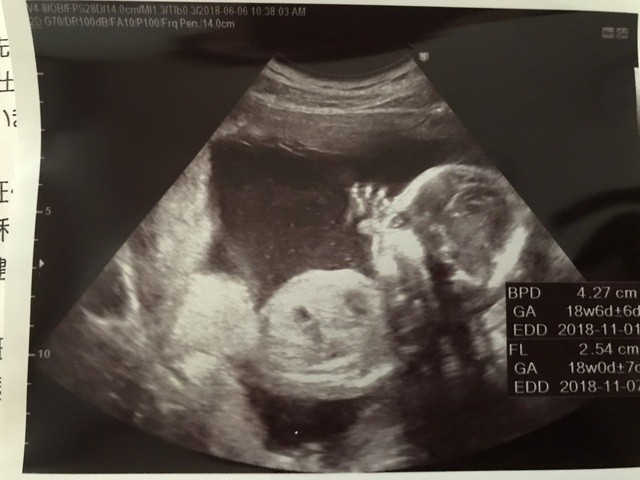

18週2日(18w2d・女の子)|ku_yan16 さん(29歳)

エコー写真撮影時のエピソード:

三人目となるお腹の赤ちゃんが女の子だとわかった日にいただいたエコー写真。女の子と思って写真を見ると、確かになんとなくポーズが女の子らしいね、とその場にいた助産師さんや医師とお話ししました。

産まれてからも頰付近に手を持っていく同じポーズをよくしているので、お腹の中にいた時からのお気に入りポーズなのだと思います。